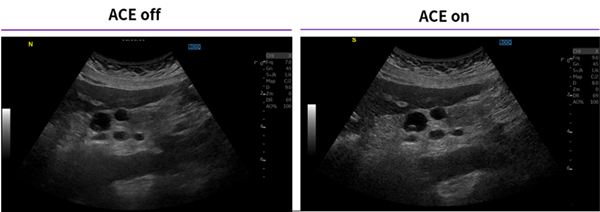

特長<2>

組織や臓器に応じて最適化されたチューニング ACE

膨大なデータからノイズ部分と組織部分の位相の歪みを判断し,ノイズを落とし,組織の信号を選択的に強調。ピクセル&フレーム毎にリアルタイムな調整が可能で,対象臓器や走査断面に合わせて適応したイメージチューニングです。